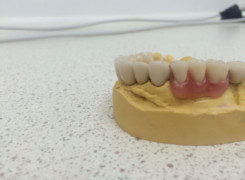

Pan Ryszard trafił do Naszego Gabinetu z jasno sprecyzowanym oczekiwaniem. Miał 84 lata i chciał odzyskać możliwość swobodnego spożywania posiłków oraz poprawienia sobie komfortu życia a także prosił aby przywrócić mu piękny uśmiech jakim cieszył się przed laty. Już na początku pierwszej rozmowy zastrzegł, że interesuje go wyłączenie rozwiązanie uzupełnieniem protetycznym stałym. Nie miał zamiaru użytkować żadnych protez ruchomych. Mając na uwadze powyższe wykonaliśmy Panu Ryszardowi zdjęcie pantomograficzne oraz badanie tomograficzne szczęki i żuchwy na postawie których zapanowywaliśmy Pacjentowi optymalne rozwiązanie – stałe uzupełnienie protetyczne w postaci 28 koron cyrkonowych zamontowanych do dwóch belek cyrkonowych które będą przymocowane do 16 implantów w konfiguracji 8 wszczepów w szczęcie 8 w żuchwie. Po omówieniu powyższego planu przystąpiliśmy do Wspólnej pracy której efekty w poszczególnych etapach prezentujemy poniżej.